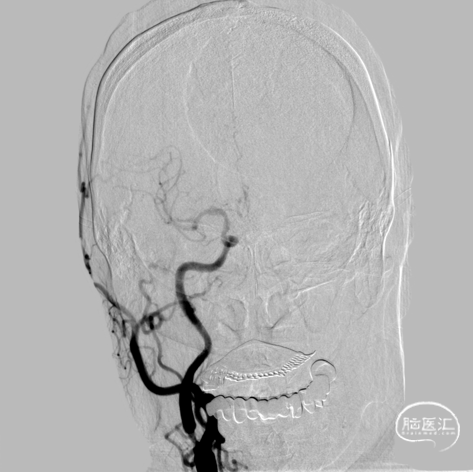

术后造影-重度狭窄70%,远端血流速度明显改善。

术前术后对比。